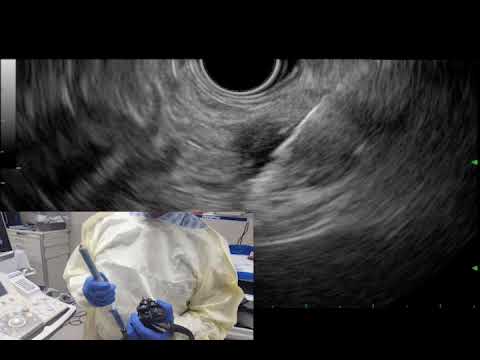

Live EUS-Guided Liver Biopsy (unedited) performed by Dr. Saurabh Mukewar